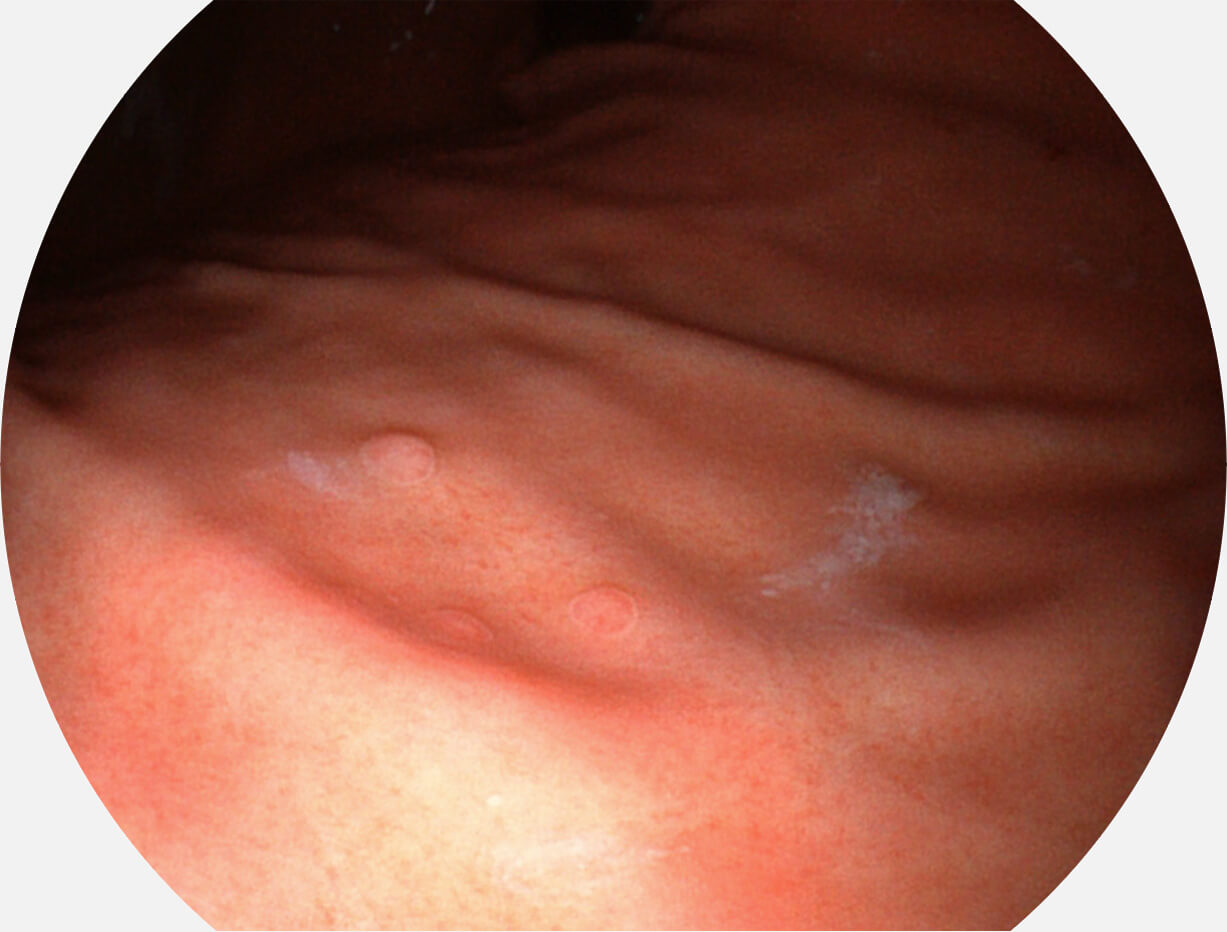

白光图像

VIST图像

强调浅层黏膜结构的同时,保证照明亮度和提升浅层微血管与中层血管颜色对比度,病变边界更清晰。